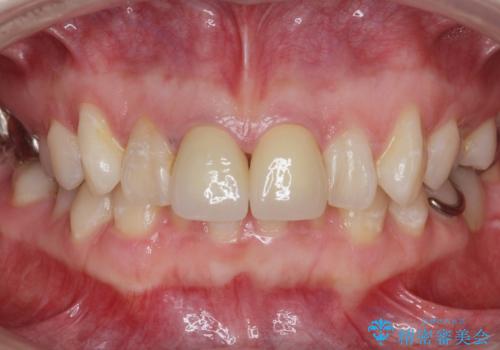

色のバランスもよく、適合も良い被せ物が入りました。

根管治療をした後、樹脂で埋めるだけで治療を終えてしまうと歯質と樹脂の隙間から細菌が入り込み、う蝕や根の感染の再発に繋がります。

適合の良い被せ物を入れることで再発リスクが低くなります。